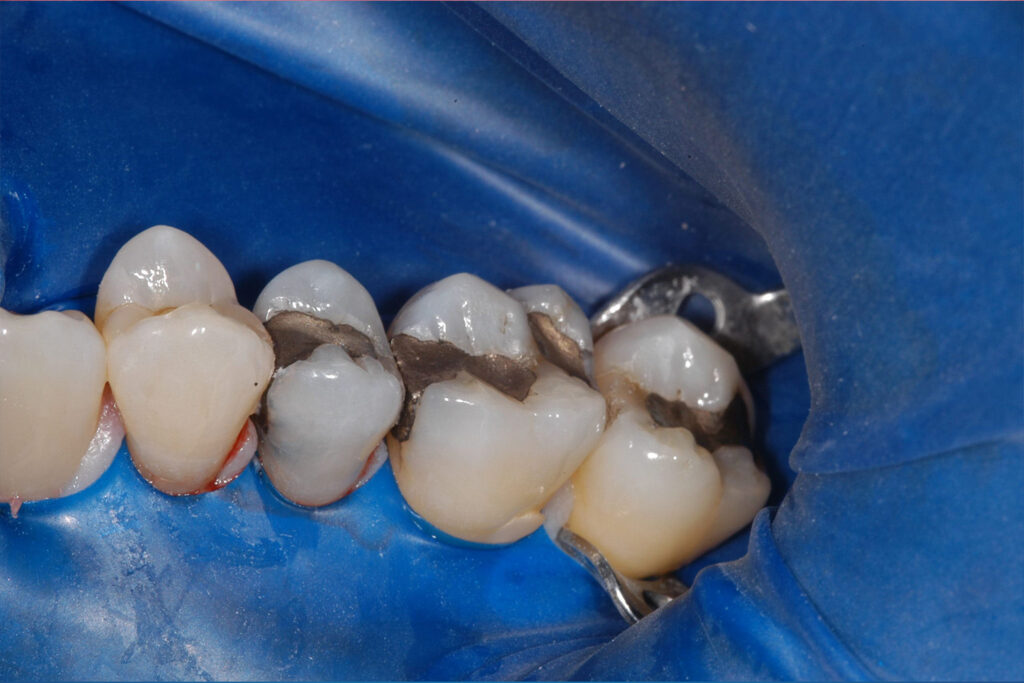

A tooth filling is a dental procedure that is used to repair a tooth that has been damaged by decay, injury, or wear.